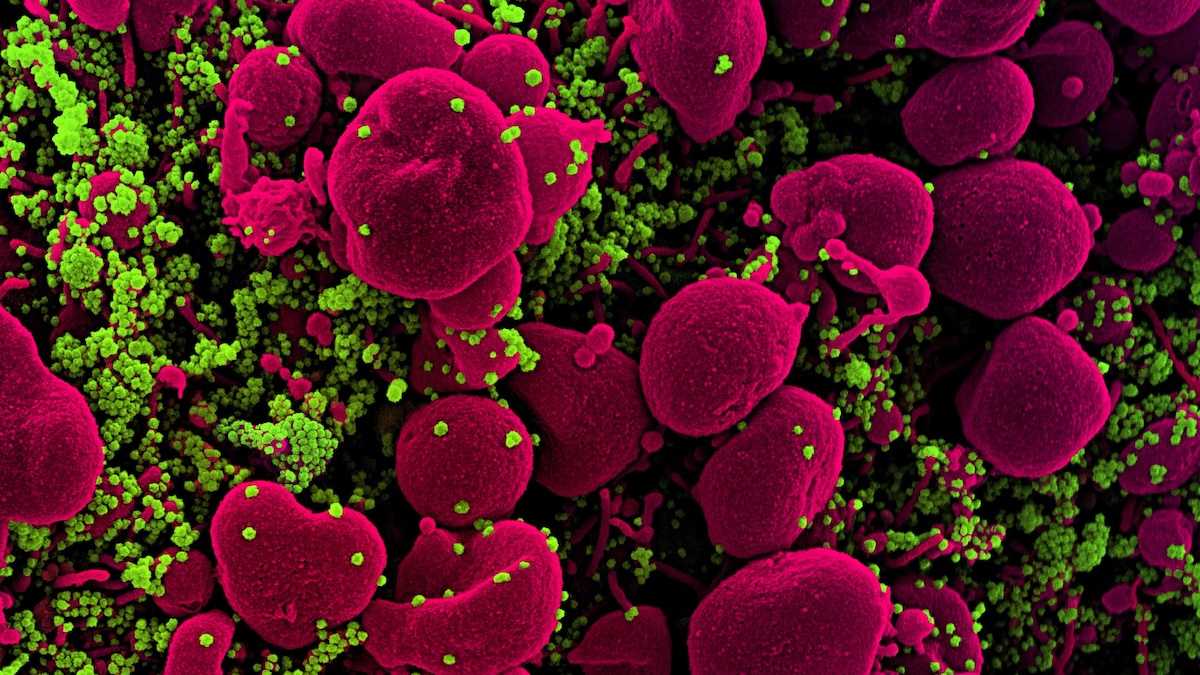

Viruses That Jump to Humans Don't Need Special Mutations, Study Finds - sciencealert.com

When a virus jumps to humans from another species, it can seem like a supervillain bent on world domination especially if it goes on to ignite a pandemic, as many zoonotic viruses have done in rece...